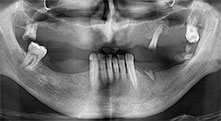

Professor Dr Emanuel Bratu, maxillofacial surgeon, oral surgeon and prostheticist, is head of the implantology departments at two Romanian Universities. He runs a renowned private hospital in Timisoara and is an internationally known researcher. In the interview Bratu explains why he considers that the W&H Piezomed piezosurgical device, and particularly two patented saws, have become essential for bone surgery.

Professor Bratu, what is your experience with the new B6/B7 saws for the W&H Piezomed?

Bratu: These saws feel completely different from previously available piezosurgical instruments. They are really astoundingly effective. We noticed immediately that the Piezomed B6/B7 work much faster than other saws. They are also easier to guide in bone, particularly in thick bone layers.

For what indications do you use the saws?

Bratu: We routinely use the instruments for harvesting bone blocks and splitting alveolar ridges. We also use the Piezomed B6/B7 for osteotomy of impacted teeth and removing failed implants. All indications that require deep, clean cuts.